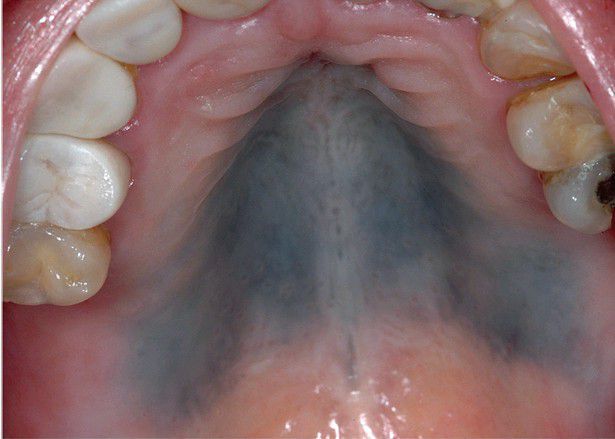

Hydroxychloroquine Pigmentation.

Diffuse grayish pigmentation of the hard palate.

Palate

Pigmentation

Hard